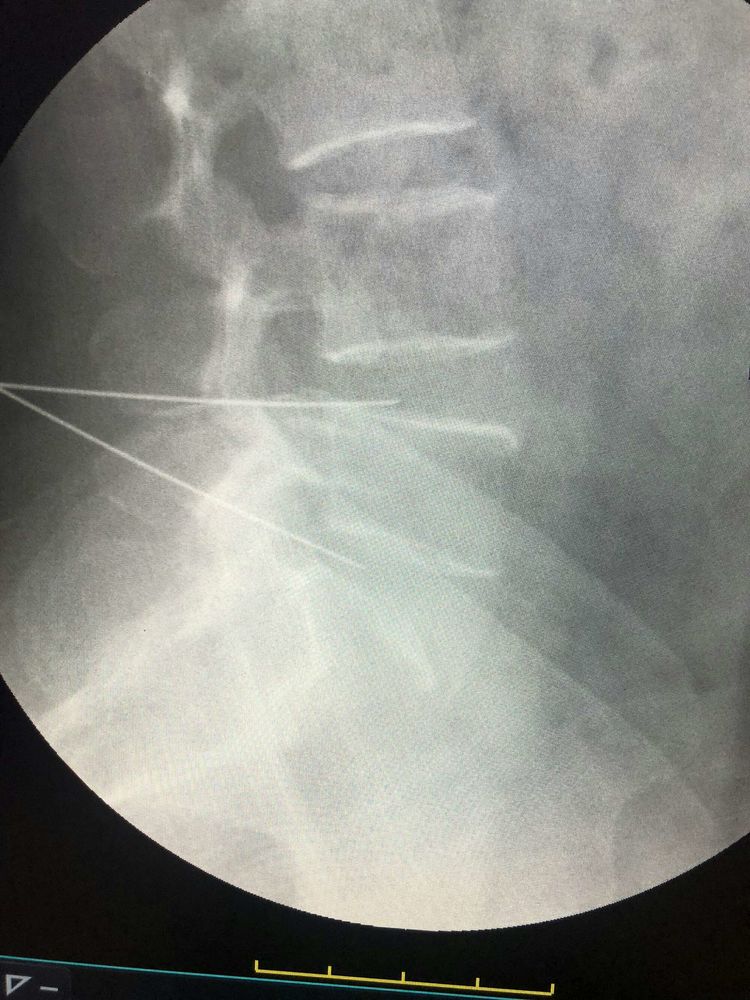

赵清臣主任经皮穿刺骨水泥椎体成形术手术中

李明治主任:椎间盘突出椎间孔镜手术治疗,术前直腿抬高30度,术后直腿抬高试验阴性,直腿抬高90度。

刘学新医生椎间孔镜手术中